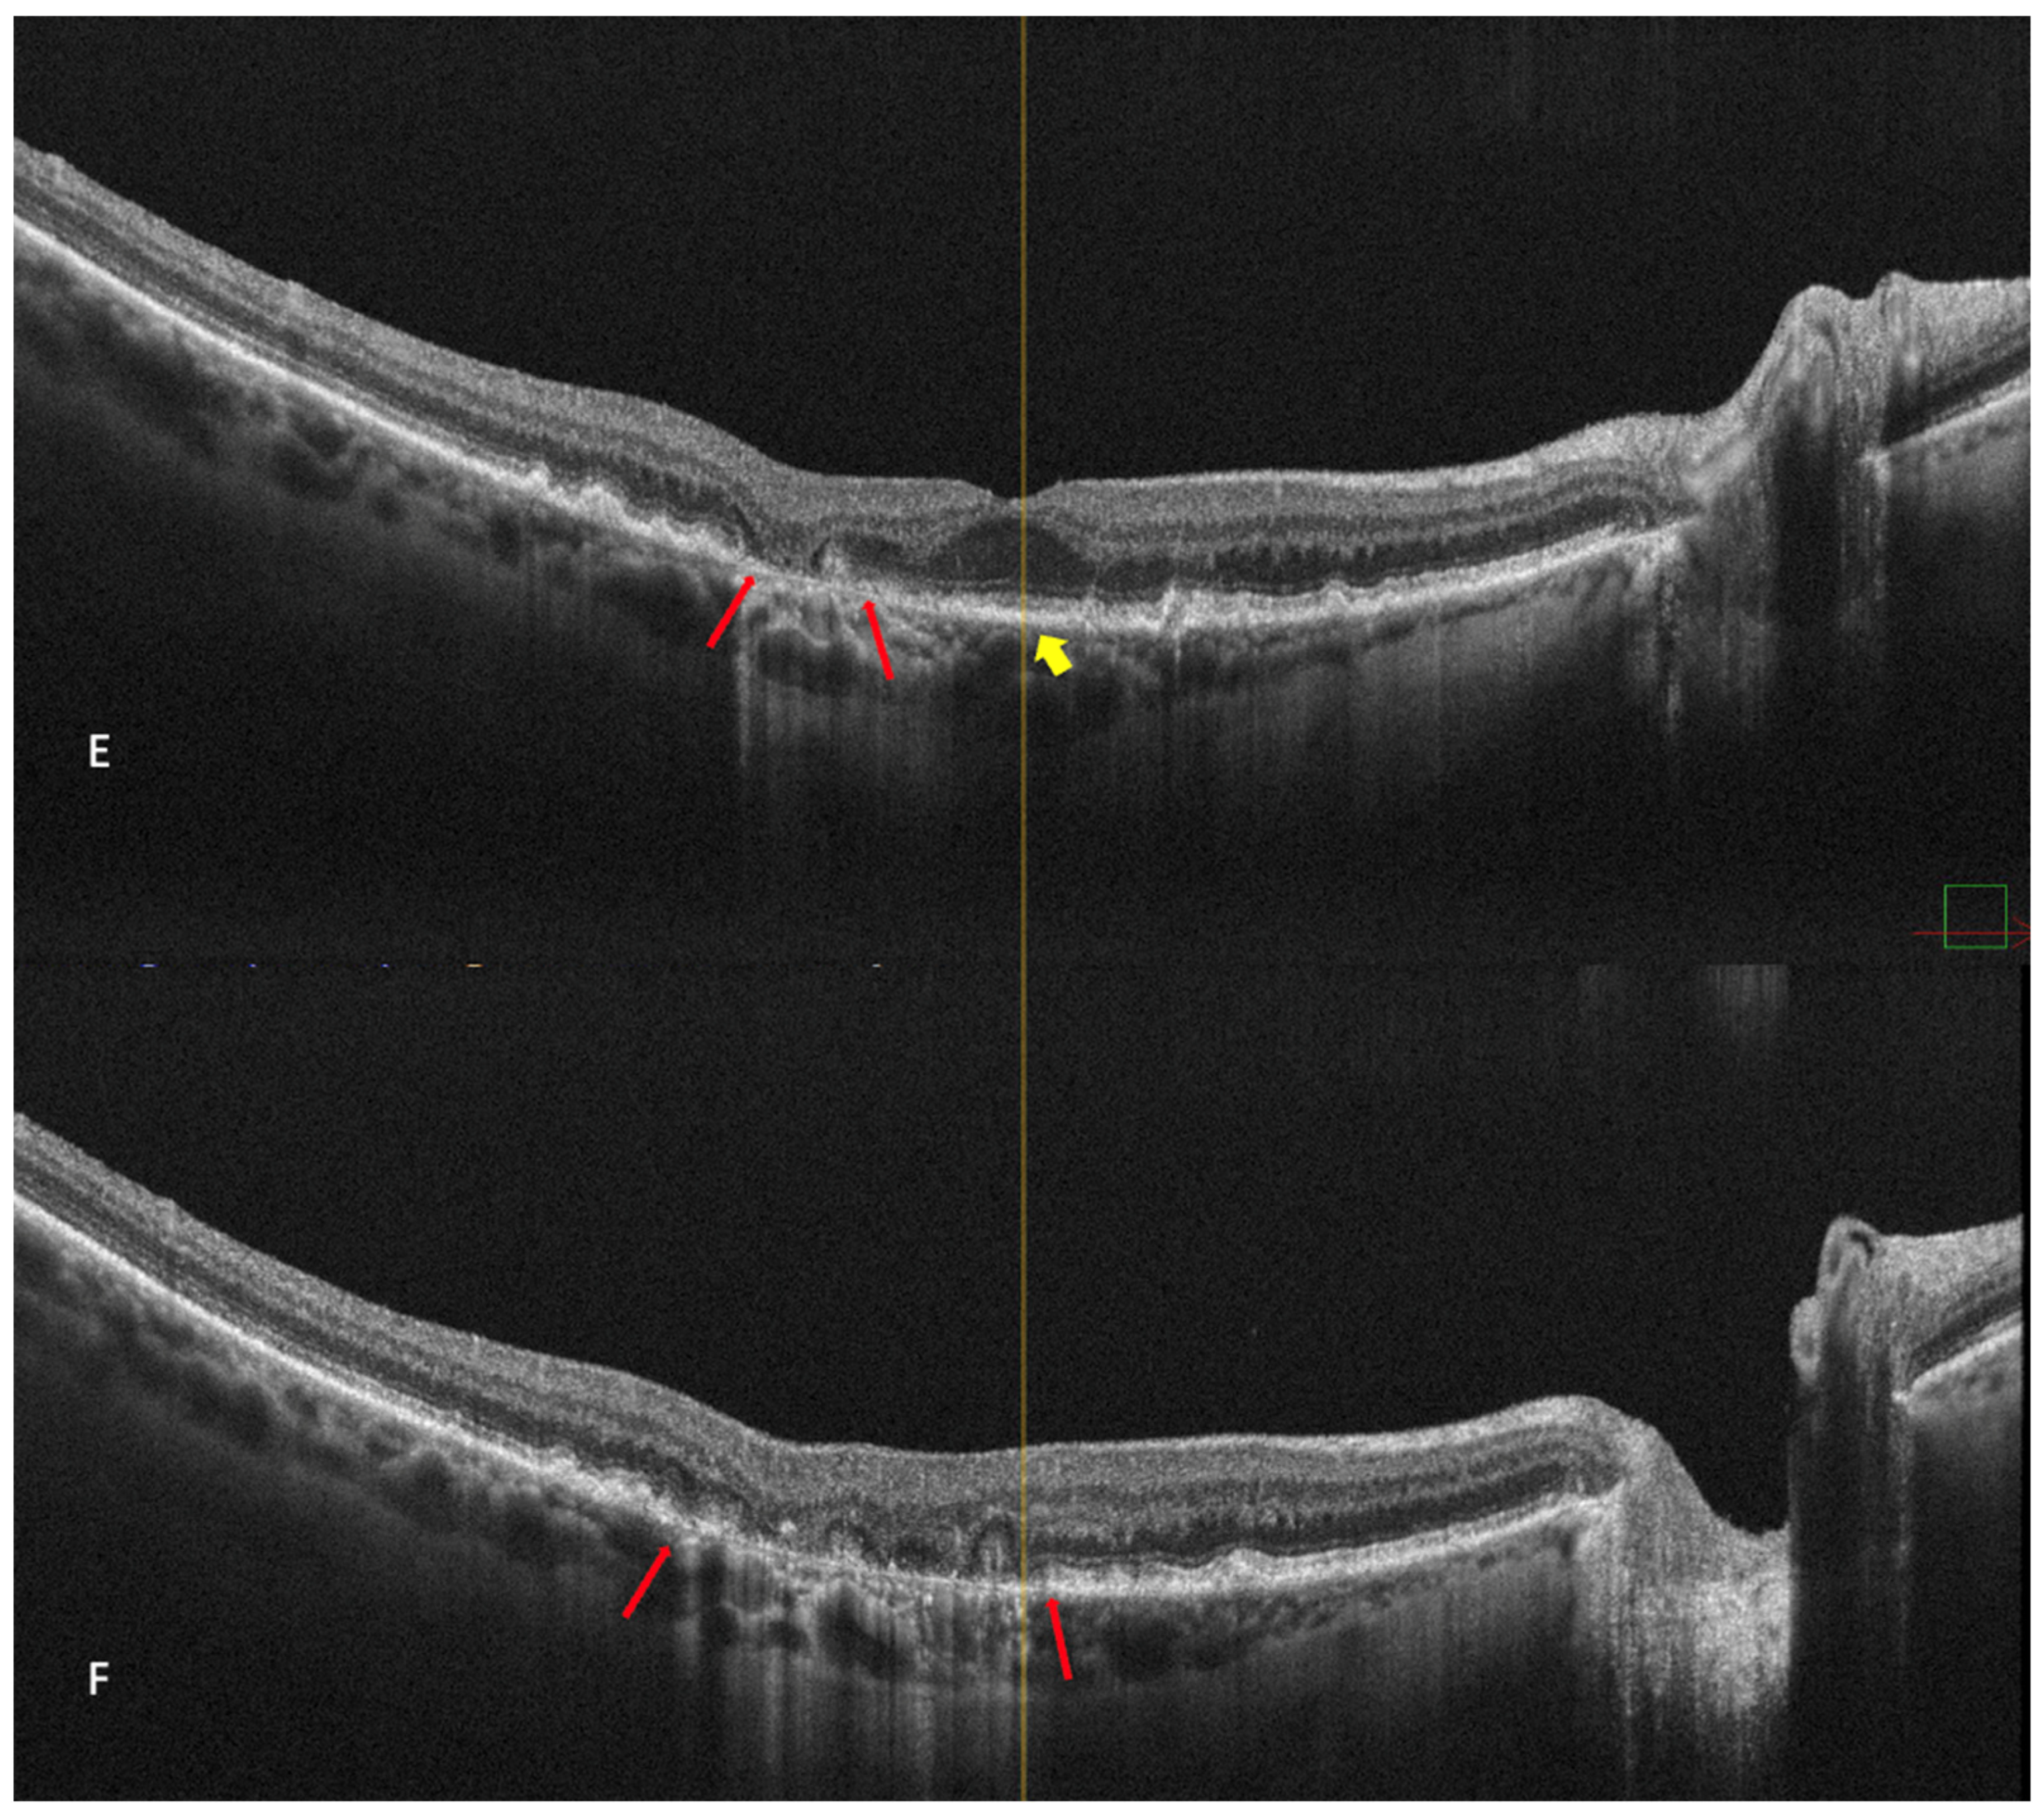

Figure 4.

(A) On the retromode image DR dot SDDs are round, hyporeflective lesions, and ribbon SDDs are difficult to see. (B) Retromode image DL shows each dot SDD as “hyporeflective core” with a “hyperreflective halo” [24], while the ribbon SDDs tend to have a reticular structure. (C) SD-OCT shows dot SDD (red arrow), ribbon SDDs (yellow arrows), and also a hyper-reflective layer on the retinal surface.

Parravano et al. conducted a study on reticular pseudodrusen imaging. Considering the characteristics of the lesions by their aspect on retromode images, the deposits were classified as round, bended, or interlacing [31].

Cozzi et al. investigated the accuracy of different retinal-imaging modalities in AMD patients. The study found that dot SDDs are hard to detect with retromode because of their high resemblance to small drusen, so the method’s accuracy is reduced in both DR (64.6% sensitivity; 85.7% specificity) and DL (76.6% sensitivity; 83.3% specificity), in comparison to other investigations [24]. The authors also specified that the DR or DL modes might not be able to detect ribbon SDDs due to their small size [24].

Dot SDDs in the retromode DR mode appear as pseudo3D round, hyporeflective lesions, and in the DL mode, they appear to have a target aspect—a hyperreflective halo surrounding a hyporeflective center. Ribbon SDDs are hardly detectable in the retromode illumination DR, and in the DL mode, they have a “reticular pattern” [24].